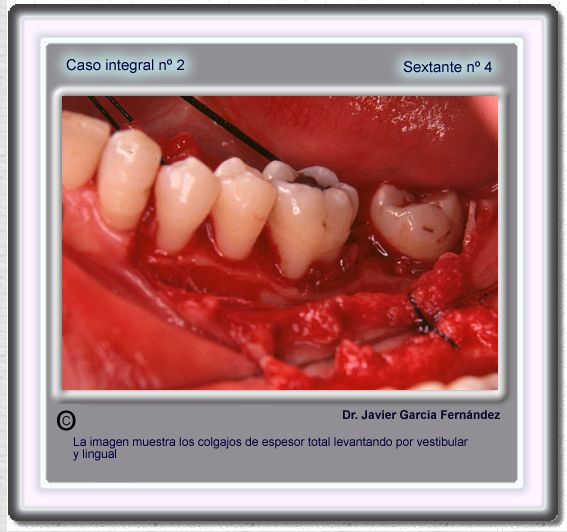

image 52